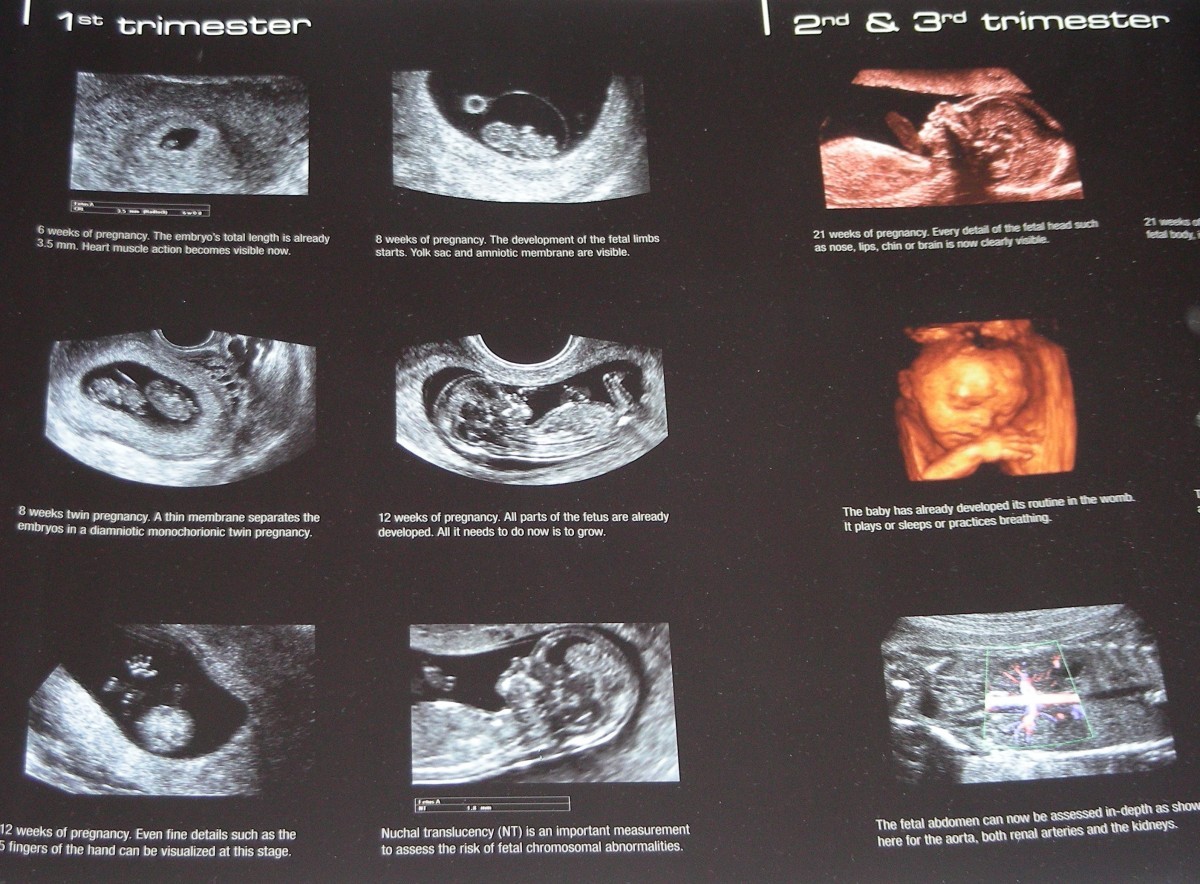

ultrazvukové vyšetrenia,